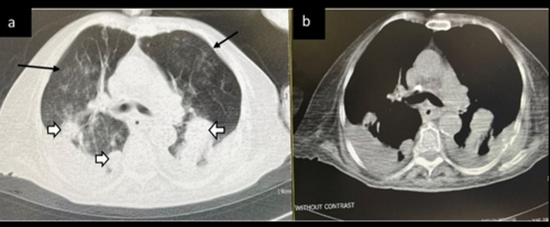

Results: The mean age was 56.48 (± 18.59), and 53% were men. Gastrointestinal (29.3%), hematologic (26.3%), and breast (10.5%) cancers were the most frequent types of cancer. The prevalence of atypical or indeterminate findings in the chest CT was 42.8%. Most radiologic findings were consolidation mixed with ground-glass opacity (44.4%), pleural effusion (33.5%), and pure ground-glass opacity (19.5%). The risk of death was higher among those who had typical chest CT for COVID-19 (OR 3.47; 95% CI 1.14-8.98) and those who had a severity of score higher than 18 (OR 1.89; 95% CI 1.07-3.34). Also, presence of consolidation (P value 0.040), pleural effusion (P value 0.000), centrilobular nodules (P value 0.013), and architectural distortion (P value 0.005) were associated with a poorer prognosis.

Conclusion: Less than half of COVID-19 patients with a history of cancer had typical imaging features of COVID-19. Radiologists should be aware of atypical, rare, or subtle chest CT findings in patients with pre-existing cancer.